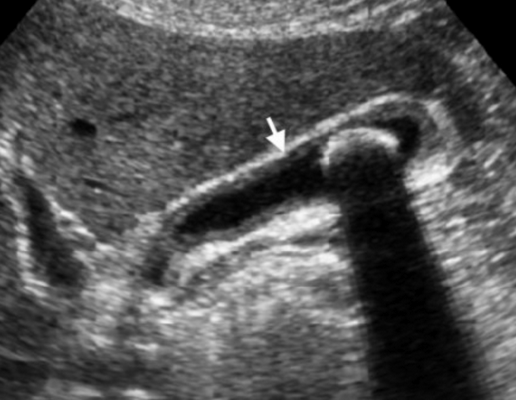

(Левый) Пример неполного кальциноза: у женщины 67 лет, жалующейся на боли в правом верхнем квадранте живота после еды определяются отдельные гиперэхогенные очаги передней и задней стенок желчного пузыря, отбрасывающие неоднородную тень.

(Правый) Пример неполного кальциноза: у мужчины 61 года в стенке желчного пузыря визуализируются точечные кальцинаты. Выявленные при патологоанатомическом исследовании конкременты не визуализируются.